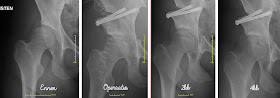

PAO:n 4kk "synttäreitä" juhlistettiin viime viikolla välikuvilla ja ihan hyvältähän tuo operaatio alkaa näyttämään. Periaatteessa olen siis nyt rajoitteeton, paitsi kovalla juokseminen on vielä kielletty pari kuukautta. Ei siis mitään lenkkiä yms. ulkona vielä kävelyä kovempaa. Tokihan minun piti sitten agilitystä kysyä, että mitenkä joustavalla keinonurmella, niin kohtuudella sitä sitten. Työtä on vielä ihan kamalasti edes normaaliin liikkeeseen, mutta jatketaan harjoituksia! Tämän kunniaksi pistimme ilmon sisään sitten Vantaan eo-hallikisoihin, joten tulemme sinne sitten tekemään vajaan puolen vuoden breikin jälkeen kisacomebackin :) Tavoitteita ei ole muuta, kuin fiilistellä.